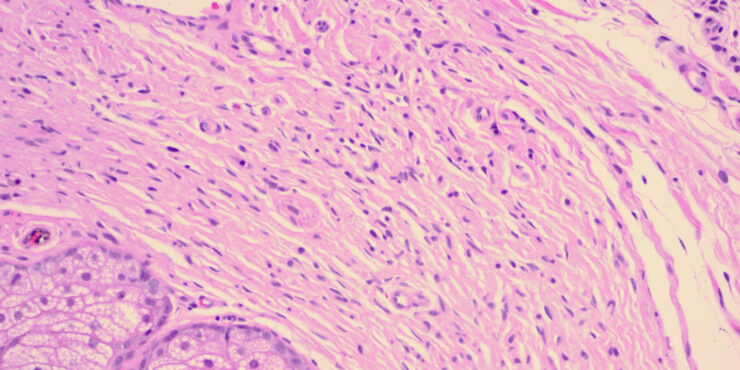

Necrobiois lipoidica diabeticorum = النخر الشحماني السكري Necrobiosis Lipoidica Necrobiosis lipoidica is an idiopathic disorder typified by indurated plaques of the shins . In 1966, in a large series, Muller and Winkelman reported that two thirds of patients with necrobiosis lipoidica had overt diabetes at the time of diagnosis {82}. Of the rest, all but […]